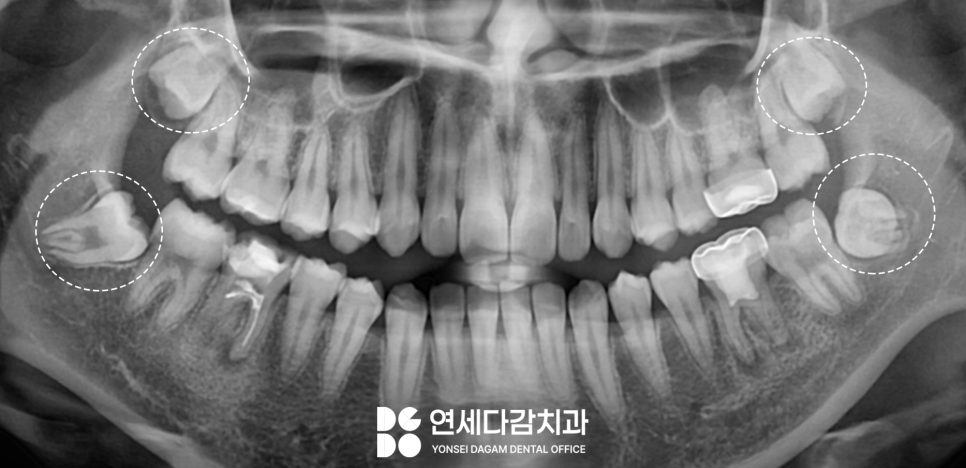

제3대구치라고 불리는

사랑니는 1개부터 4개까지 존재하며

아예 없는 경우도 있습니다.

4개가 다 있다고 해서

꼭 빼야 되는 것은 아닙니다.

다만 문제가 생겼거나

생길 것으로 우려될 때,

또는 교정치료를 받기 전

검사 결과 사랑니가 방해요소가 되어

발치가 필요하다는 진단을 받는

경우가 있습니다.

대부분의 사랑니 발치는

비교적 단순한 과정이지만,

때로는 방향과 위치가

예상과 다를 때 복잡한 케이스로

분류되기도 합니다.

일반적으로 매복 사랑니가

존재한다면 누워있는 수평

형태일 때가 많습니다.

이러한 복잡한 케이스에서는

CT 촬영을 통해 3차원적인

구조 분석을 통해

안전한 발치 전략을

미리 수립하는 것이

필수 과정입니다.